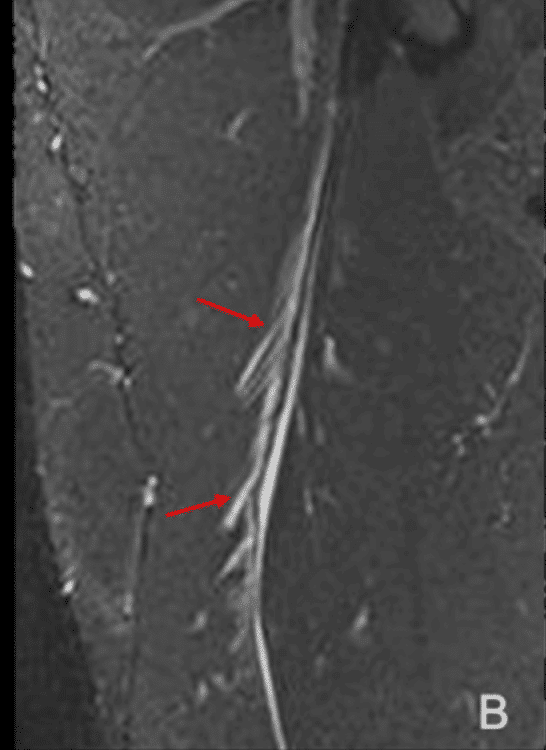

・Ⅱ型3度

(Pedret C, J Belg Soc Radiol. 2022から引用)

全周性に腱膜の連続性が確認できない

(奥脇 透:大腿二頭筋肉ばなれの MRI 分類、臨床スポーツ、2019より引用)